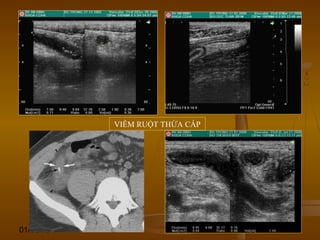

DẤU HIỆU BIA BẮNDẤU HIỆU BIA BẮN

(TARGET SIGN)(TARGET SIGN)

 Hình ảnh những vòng đồng tâm hồi âm dày và hồiHình ảnh những vòng đồng tâm hồi âm dày và hồi

âm kém xen kẽ hoặc là vòng tròn hồi âm kém vớiâm kém xen kẽ hoặc là vòng tròn hồi âm kém với

trung tâm hồi âm dày.trung tâm hồi âm dày.

 Dấu hiệu này có thể thấy ở nhiều bệnh lý của ốngDấu hiệu này có thể thấy ở nhiều bệnh lý của ống

tiêu hóa.tiêu hóa.

 Nó có thể là sự dày lên của vách ống tiêu hóa doNó có thể là sự dày lên của vách ống tiêu hóa do

viêm (VRT, viêm ĐT giả mạc), u, thiếu máu, phìviêm (VRT, viêm ĐT giả mạc), u, thiếu máu, phì

đại (hẹp môn vị phì đại).đại (hẹp môn vị phì đại).

 Hoặc có thể là hình ảnh của các đoạn ống tiêuHoặc có thể là hình ảnh của các đoạn ống tiêu

hóa lồng vào nhau (lồng ruột).hóa lồng vào nhau (lồng ruột).

Viêm ruột thừa cấp